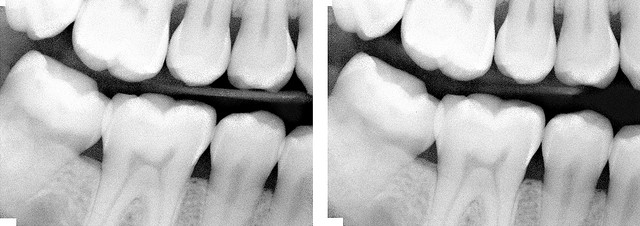

牙周病其實是現代人常發生的疾病之一,而您知道嗎? 孕婦若有嚴重的牙周病時,發生早產的機率比沒牙周病的孕婦還高,若沒及時治療,發生的機率是一般人的三倍,不可忽視。